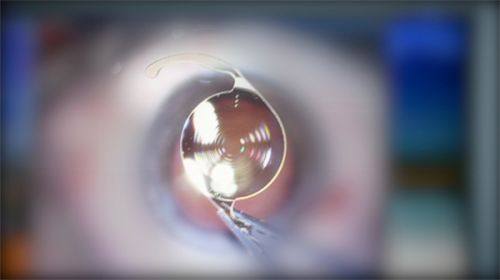

3.徐州复兴眼科医院白内障治疗成效好

白内障专科是徐州复兴眼科医院早成立的科室之一,科室拥有十余名经验多的主刀医生,经过发展已形成一支白内障诊疗团队。近年来在徐州市开展屈光白内障手术、蔡司多焦点人工晶状体、三焦点人工晶状体等新型人工晶状体植入术,满足不同患者的需求,得到广大患者的高度赞誉。